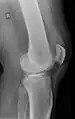

Operative image: 1. Kneecap 2. upper patella pole with drill holes 3. Stump of the quadriceps tendon